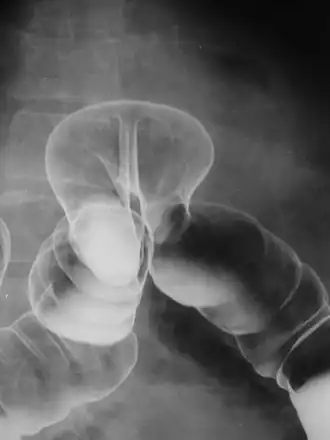

By far the most common hernias (up to 75% of all abdominal hernias) are inguinal hernias, which are further divided into the more common indirect inguinal hernia (2/3, depicted here), in which the inguinal canal is entered via a congenital weakness at its entrance (the internal inguinal ring), and the direct inguinal hernia type (1/3), where the hernia contents push through a weak spot in the back wall of the inguinal canal. An indirect inguinal hernia and a direct inguinal hernia can be distinguished by their positioning in relation to the inferior epigastric vessels. An indirect hernia is situated laterally to these vessels, whereas a direct hernia is positioned medially to them. Inguinal hernias are the most common type of hernia in both men and women. In some selected cases, they may require surgery.